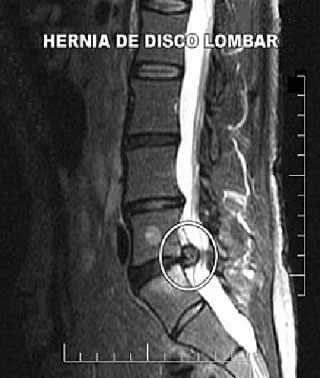

Mantida a compressão e degeneração do disco, sem tratamento, ocorre a formação da hérnia, onde o núcleo pulposo "estoura e vaza para fora" do anel fibroso (em rosa).

Hérnia de disco lombar circulada, entre Lombar 5 e Sacral 1. No disco acima, temos uma protrusão discal, estágio anterior à formação da hérnia.